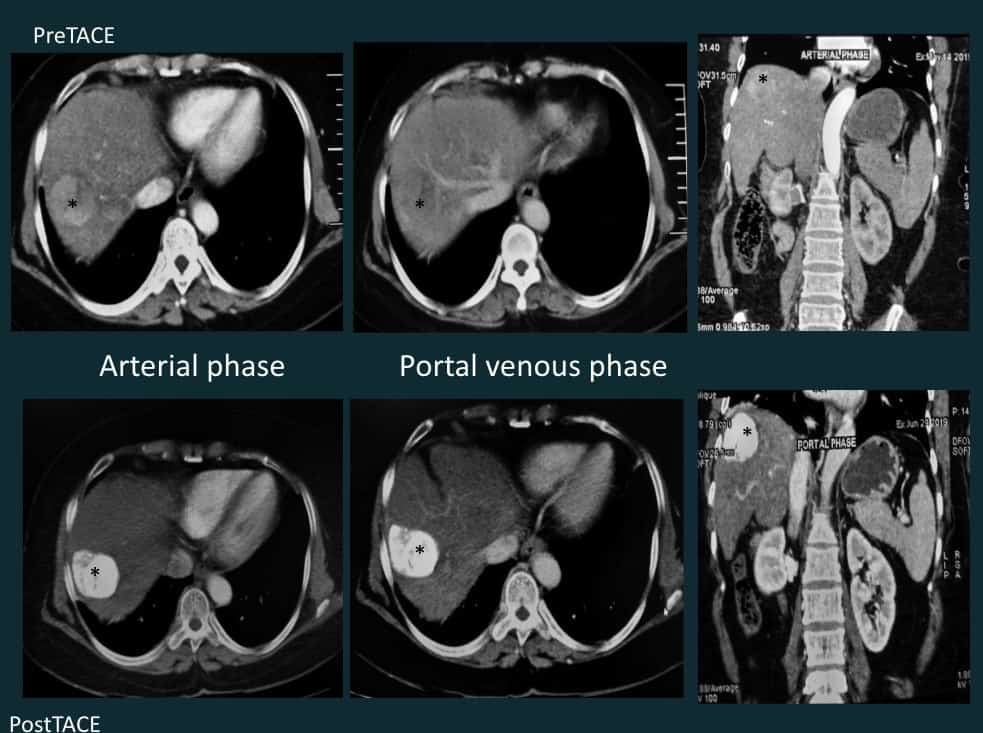

Transarterial Chemoembolization

Fifty-four-year-old lady with non-cirrhotic liver and HCC. Treated with transarterial chemoembolization (TACE). A. CECT of the abdomen – arterial phase enhancing lesion in segment VII of the liver. B. Selective celiac artery cannulation with a 4F Simmons diagnostic catheter which was advanced to the common hepatic artery (blue arrow) and a microcatheter (red arrow) was coaxially placed with the tip in the RHA. Superselective cannulation and angiogram of the feeder artery, a branch of right hepatic artery showing tumor blush (*) along with normal parenchymal branches (black arrow). C. Further advancement of the microcatheter (red arrow) to surpass the normal parenchymal branches and chemoembolization (Lipiodol and Doxorubicin emulsion in 2:1 ratio) in process. Lipiodol accumulation in the tumor stroma (*).  After chemoembolization, gel foam embolization of the feeder artery was done. Post embolization angiogram showed complete occlusion of the tumor artery with patent normal parenchymal branches (arrow). Good lipiodol โ€“doxorubicin emulsion deposit is also seen (*).

4a.TACE (contd)

Post Transarterial Chemoembolisation TACE for liver tumors HCC

TACE pre and one-month post-procedure image series show the segment VII lesion (*) with good lipiodol uptake (Type I pattern) in the tumour with no evidence of residual enhancing areas or non-target embolization.